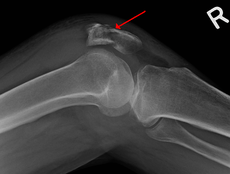

A fracture of the patella seen on a lateral view